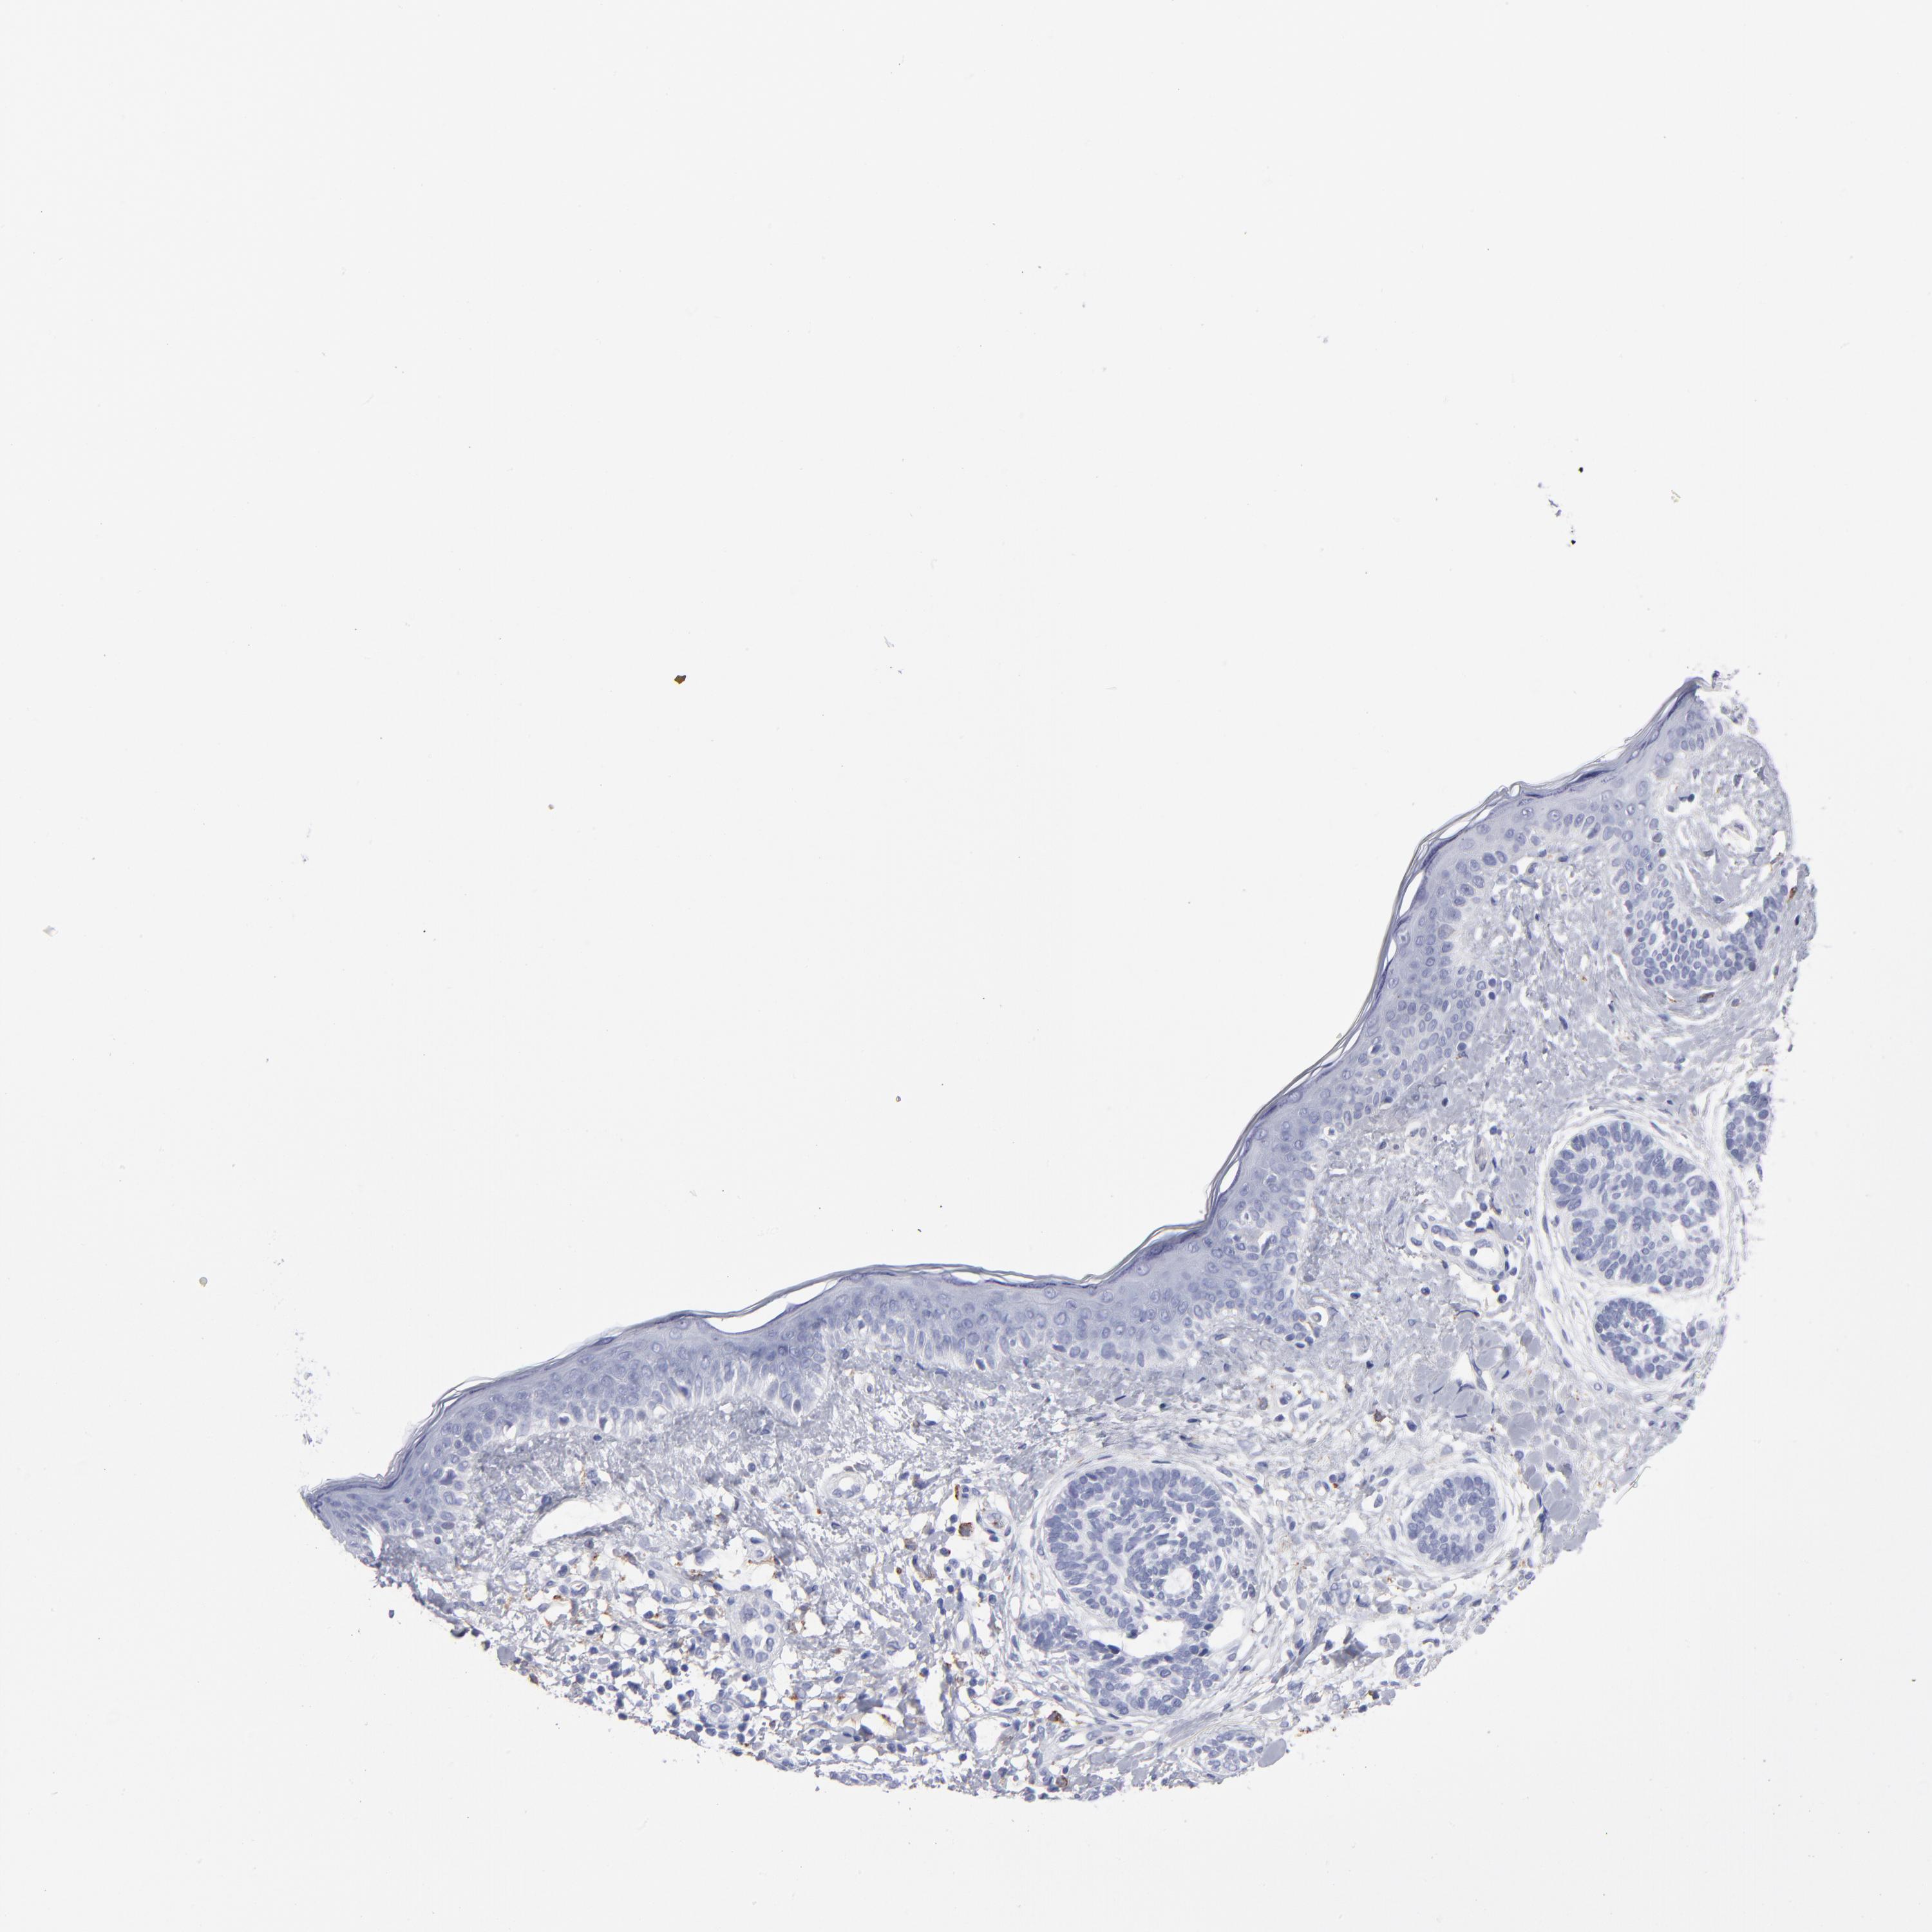

SKIN CANCER - Protein expressioni

A mouse-over function shows sample information and annotation data. Click on an image to view it in a full screen mode. Samples can be filtered based on level of antibody staining by selecting one or several of the following categories: high, medium, low and not detected. The assay and annotation is described here.

Antibody stainingi

Antibody staining in the annotated cell types in the current human tissue is reported as not detected, low, medium, or high, based on conventional immunohistochemistry profiling in selected tissues. This score is based on the combination of the staining intensity and fraction of stained cells.

Each image is clickable and will lead to virtual microscopy that enables deeper exploration of all samples and also displays staining intensity scores, fraction scores and subcellular localization as well as patient and tissue information for each sample.

Antibody HPA003740

Squamous cell carcinoma, NOS

Basal cell carcinoma